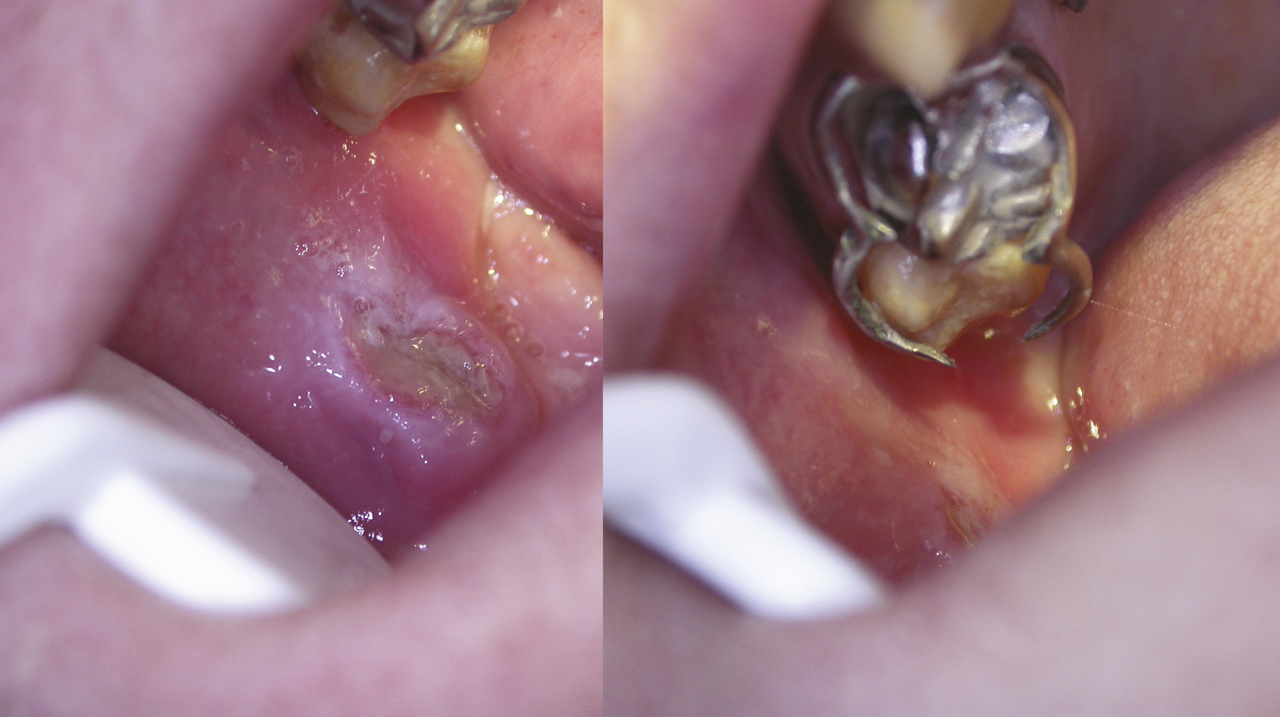

Si les aphtes banals et les traumatismes représentent les causes les plus fréquentes d’ulcérations buccales,1 leur diagnostic repose sur certaines caractéristiques cliniques et ne doit pas faire méconnaître les autres causes dominées en sévérité par le carcinome épidermoïde. L’aphte buccal est fréquent, souvent banal, ses critères diagnostiques sont précis et ce diagnostic est souvent porté par excès. C’est une ulcération le plus souvent ronde, très douloureuse, de quelques millimètres de diamètre à bords réguliers, entourée d’un halo rouge inflammatoire, son fond est jaune « beurre frais » (fig. 1 ), et il repose sur une base souple. Les aphtes siègent préférentiellement sur les muqueuses souples (lèvres, joues, langue), l’atteinte gingivale ou palatine est rare. Il guérit spontanément en une dizaine de jours. Une ulcération ne correspondant pas à cette description doit faire rediscuter le diagnostic d’aphte dans la crainte de méconnaître un diagnostic plus sévère comme un carcinome épidermoïde débutant (fig. 2 ). Un aphte « géant » est défini par un diamètre supérieur à 1 cm (fig. 3 ) ; c’est une forme sévère extrêmement douloureuse pouvant demander plusieurs semaines voire plusieurs mois pour cicatriser en l’absence de traitement. Cette forme est peu fréquente et peut être liée à une immunodépression.

L’ulcération traumatique est souvent unique, de taille variable, douloureuse à fond fibrineux et à bordure blanchâtre. Elle est souple, ne s’accompagne pas d’adénopathie satellite. L’agent traumatisant est souvent évident : carie, couronne dentaire défectueuse, prothèse inadaptée ou crochet blessant (fig. 4 ) ; sa suppression permet la cicatrisation en une dizaine de jours.